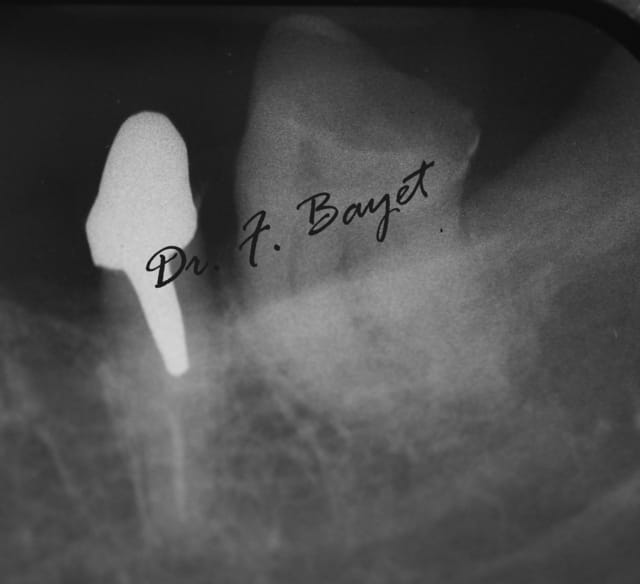

Ici avec de l'AlphaKite de chez Komet: lime 25 6% pour la 24 et Lime 25 6% puis finition 25 8% pour la 25.(moteur ATR sens de rotation horaire > antihoraire).

Img 0636 copie kylsbt - Eugenol

Moi je dis: signer ses endos comme les studios harcourt, c'est la classe.